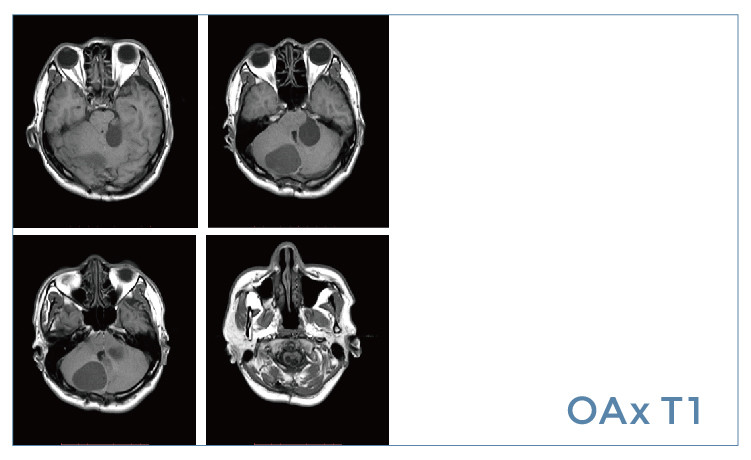

【朗润影像档案】20190614磁共振影像病例结果讨论

【朗润影像档案】磁共振影像病例分享(编号20190614)